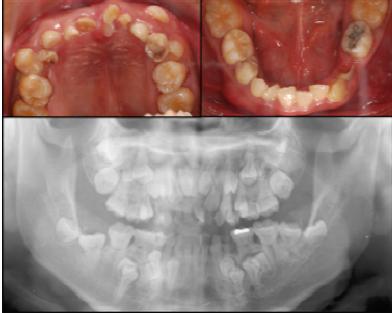

6. 20歲患者的口內齒列檢查與環口X-光影像如下圖,其最可能的臨床診斷為何?

(A)鎖骨顱骨發育不全(cleidocranial dysplasia) (B)唇腭裂 (C)半邊小臉症(hemifacial microsomia) (D)Treacher Collins症候群